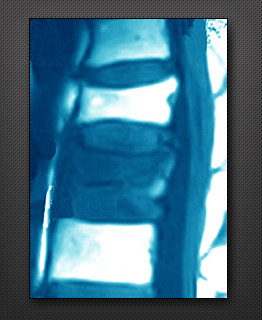

척추 전방 전위증

척추디스크와 후관절의 퇴행성 변화 또는 외상에 의해 척추마디가 불안정해져 척추뼈가 앞, 뒤로 튀어나오는 질환을 척추전방전위증이라 하며, 허리수술 환자의 15%를 차지할 정도로 디스크 다음으로 흔한 질환입니다.

보행시 다리저림, 당김, 통증, 하부요통(엉치주위) 등이 발생합니다.

척추 전방 전위증의 증례

척추 전방 전위증의 치료

요통이 주증상인 경우 운동과 함께 보조기 등으로 척추의 안정을 얻지만, 일상생활을 하기 힘들 정도의 통증이 있거나, 신경증상(마비)이 진행되면 수술이 필요합니다.수술은 요통의 호전과 하지 방사통을 제거하며 척추의 안정성을 유지합니다.